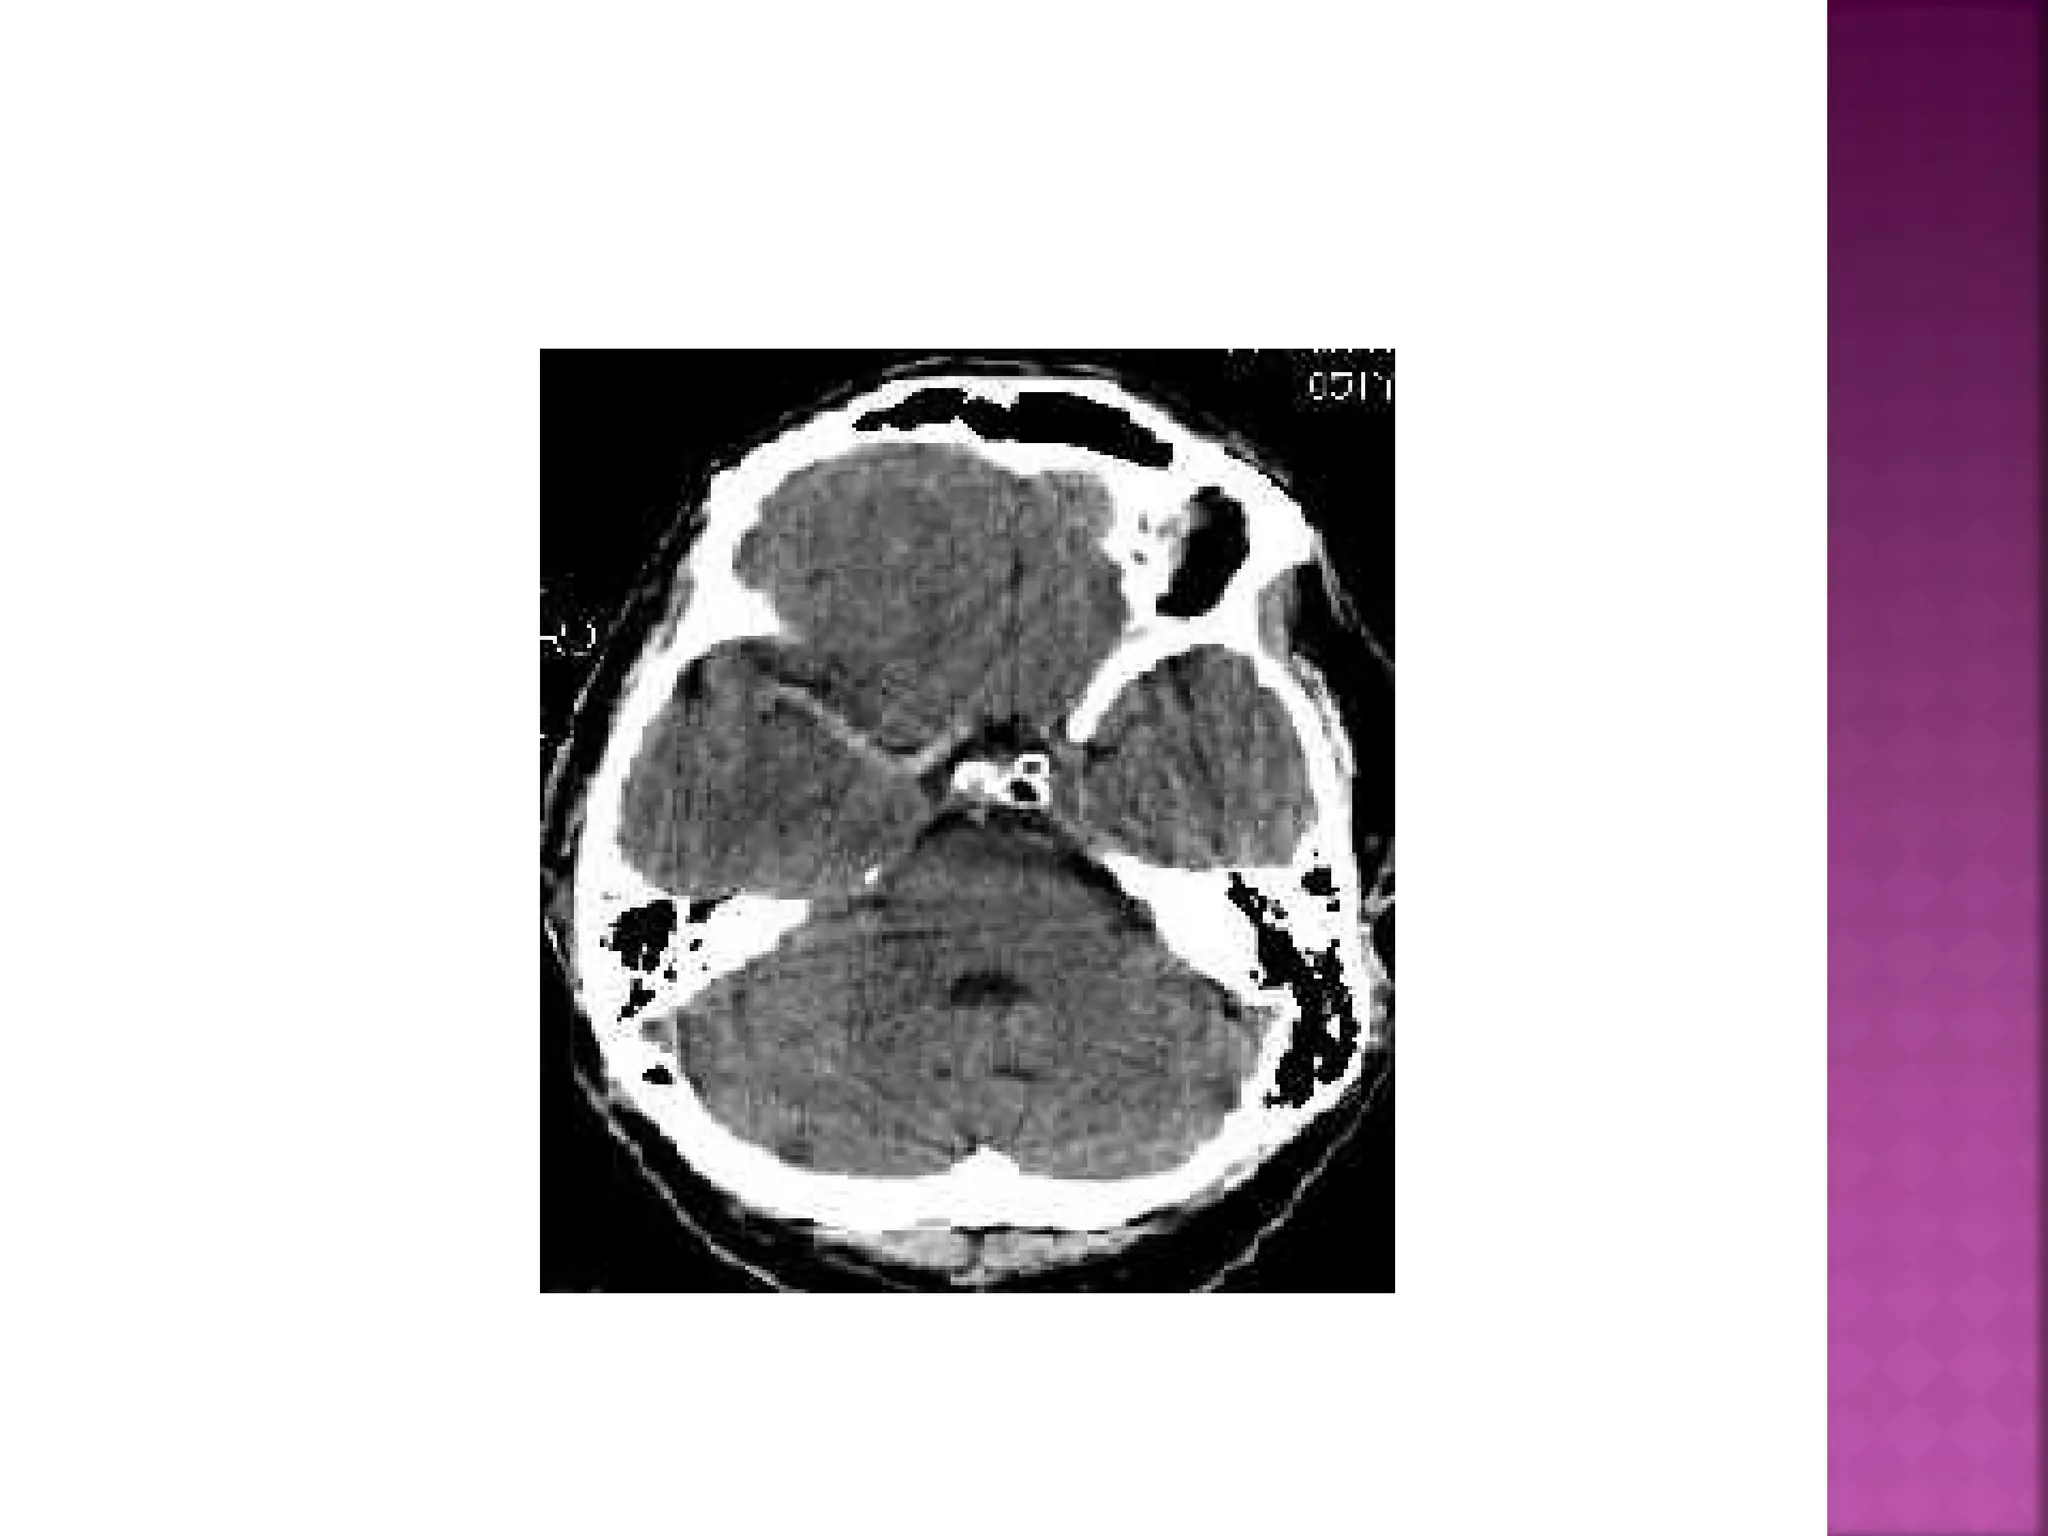

On T2WI and FLAIR infarction is seen as high

SI.

These sequences detect 80% of infarctions

before 24 hours.

They may be negative up to 2-4 hours postictus!

 On T2WI andFLAIR infarction is seen as high SI. These sequences detect 80% of infarctions before 24 hours. They may be negative up to 2-4 hours postictus!